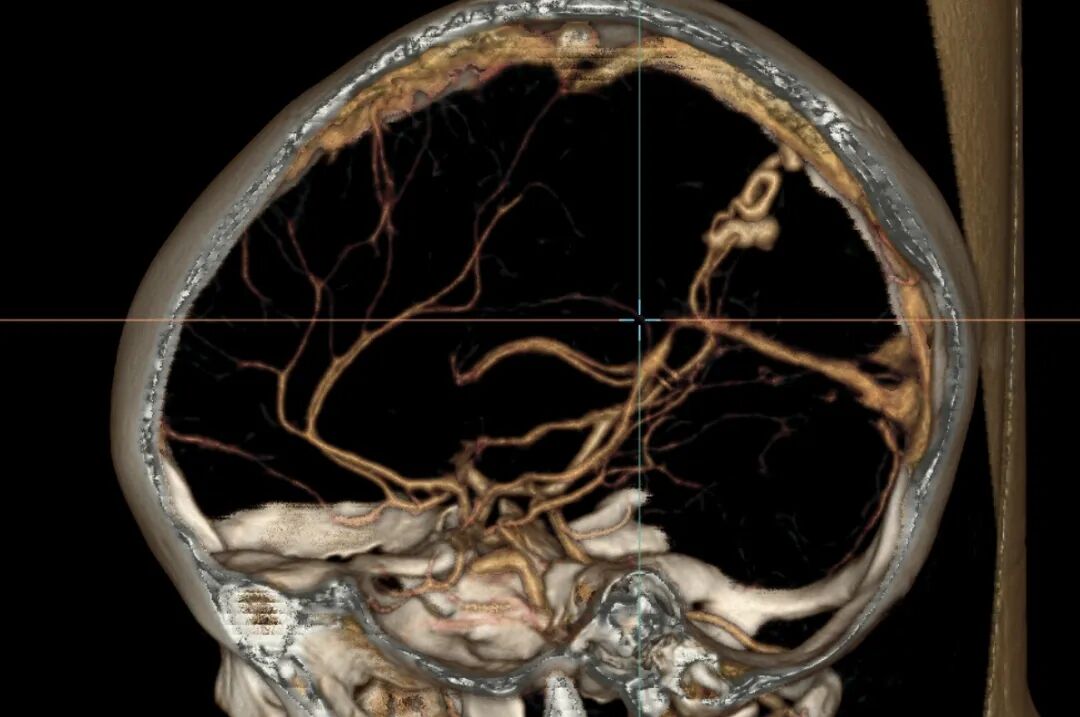

颅脑CTA显示脑内动静脉瘘和动脉瘤

为明确诊断,紧急为婷婷安排了颅脑CTA(CT血管造影)检查,结果显示,婷婷右侧大脑后动脉供血的脑动静脉瘘合并动脉瘤,且动脉瘤已破裂出血,这正是导致突发昏迷和偏瘫的 “元凶”。这是一个极其罕见的脑血管畸形:脑动静脉瘘合并血流相关性动脉瘤,且动脉瘤已经破裂,脑动静脉瘘与动脉瘤并存更是增加了救治难度:瘘口导致血液异常分流,动脉瘤随时可能再次破裂,而60ml 的血肿已压迫脑组织,每延迟一分钟,神经功能损伤的风险就增加一分。面对如此复杂的病情,手术难度极高。